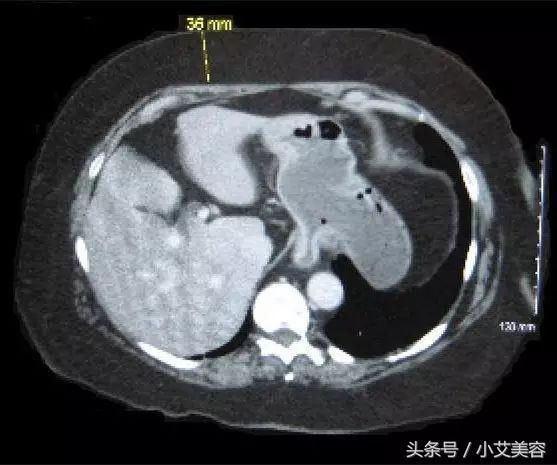

我们来看下面这个腹部CT图片,这是平常人的腹部剖面图。

下面是肥胖者的腹部,可以看到黄色虚线表明的地方足足有3.6厘米厚的脂肪。